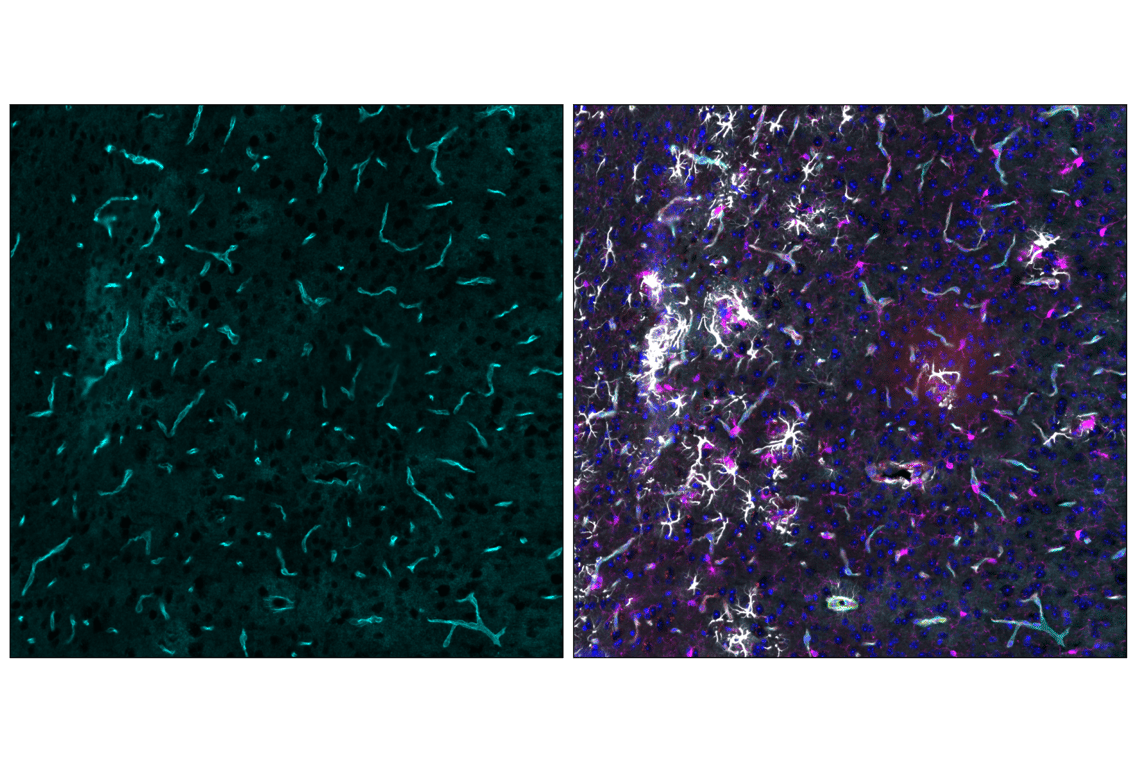

Cyclic multiplex immunofluorescent analysis of fixed frozen thalamus from an amyloid mouse model of Alzheimer's Disease using CD31 (PECAM-1) (F2N3M) Rabbit mAb #15585 (red). After blocking free secondary antibody binding sites with Rabbit (DA1E) mAb IgG XP® Isotype Control #3900, the tissues were then labeled using α-Smooth Muscle Actin (1A4) Mouse mAb (Alexa Fluor® 488 Conjugate) #46469 (green) and  AQP4 (D1F8E) XP® Rabbit mAb (Alexa Fluor® 647 Conjugate) #89851 (cyan). Sections were mounted in ProLong Gold Antifade Reagent with DAPI #8961 (blue) and then imaged. After imaging, sections were processed in Western Blot Stripping Buffer (5X) #91925 to remove bound primary and secondary antibody. Then sections were labeled with GFAP (E4L7M) XP® Rabbit mAb (Alexa Fluor® 488 Conjugate) #94242 (gray) and Iba1/AIF-1 (E4O4W) XP® Rabbit mAb (Alexa Fluor® 647 Conjugate) #78060 (magenta). Sections were mounted in ProLong Gold Antifade Reagent with DAPI #8961 (blue) and then imaged a second time.

Immunofluorescence Image 4: AQP4 (D1F8E) Rabbit Monoclonal Antibody (Alexa Fluor<sup>®</sup> 647 Conjugate)